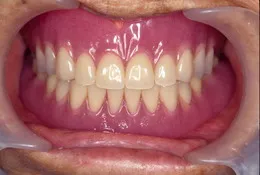

総入れ歯で肝心なのは顎(顎堤)にぴったりあっていることと咬み合わせがしっかりしていることでしょう。入れ歯で困っている方には原因があります。丁寧に診査し解決策を探りましょう。

当院では治療用の入れ歯を使って顎にぴったりとあった形を導きます。ぴったりあった入れ歯を入れると口元も自然感を取り戻せます。「急がばまわれ」、少し時間をかけて使いやすい入れ歯を手に入れましょう。

(顎の形にしっかりフィットして咬み合わせが安定した入れ歯ができあがりました)